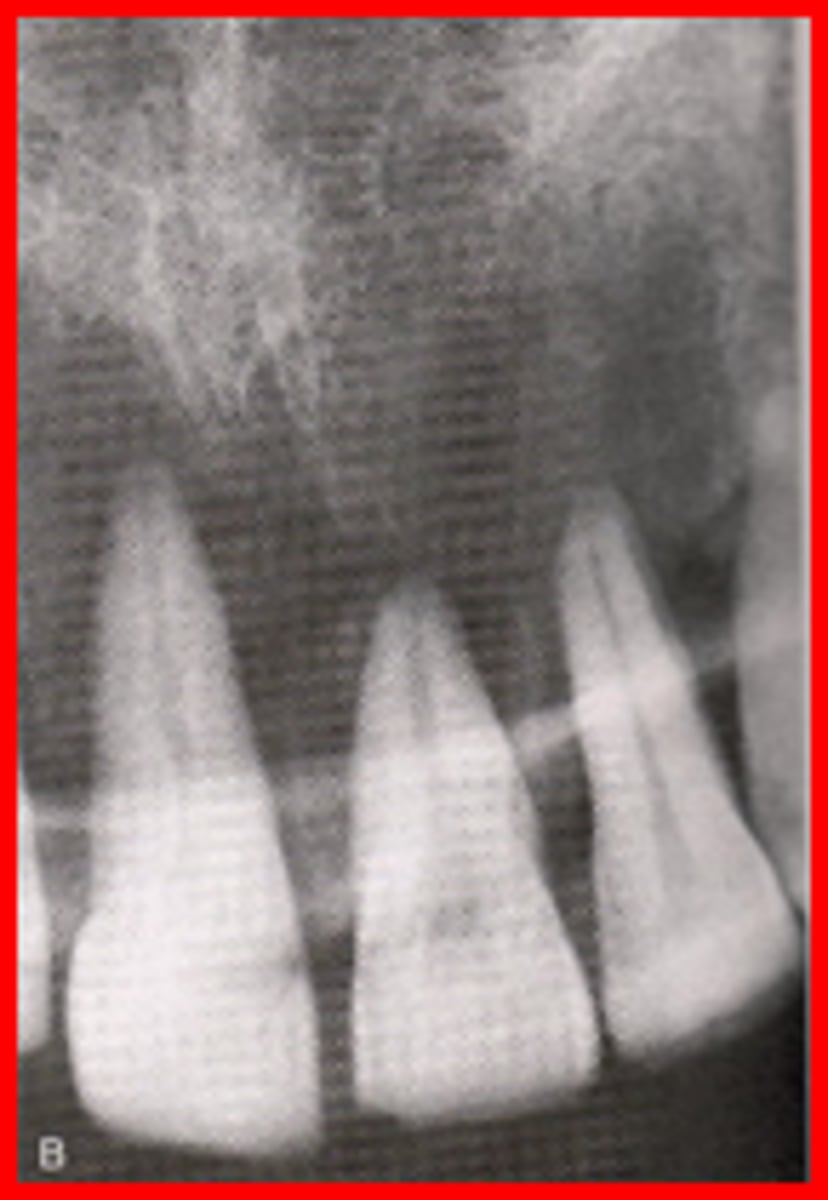

Foreshortened image

results from excessive vertical angulation

Elongated images

results from insufficient vertical angulation

Correct vertical angulation

Results in a radiographic image that is the same length as the tooth

Incorrect vertical angulation

Results in a radiographic image that is not the same length as the tooth